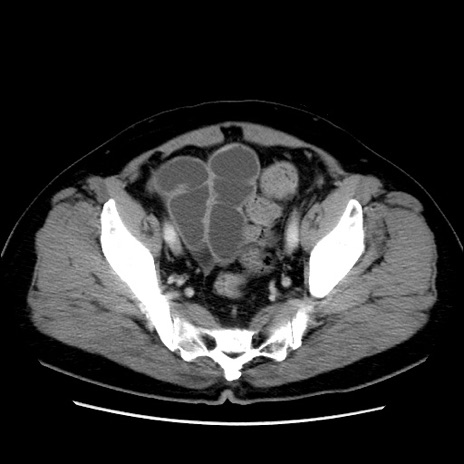

症例16(横断像)

【症例】 70歳代男性

【主訴】 腹痛、嘔吐

【現病歴】 約1ヶ月前より間欠的に腹痛と嘔吐あり、当院消化器内科を受診したところCTで多発する肝臓のLDAを指摘され、精査中であった。以降は消化器症状は安定していたが、2日前より嘔気と腹痛があり、同日より排便・排ガスが消失した。改善認めず、 本日、救急外来を受診した。

【既往歴】 大腸ポリープ切除後。

【身体所見】意識清明・会話良好、BT 36.3℃、BP 127/80mmHg、 P 80bpm、腹部:膨満あり、平坦・軟、上腹部正中および下腹部正中に圧痛あり、反跳痛なし、筋性防御なし。

【データ】WBC 7200、CRP 0.77